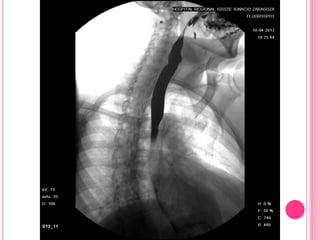

Estudio baritado en paciente con esclerodermia que desarrolló esofagitis

severa por reflujo por la incompetencia del esfínter esofágico inferior